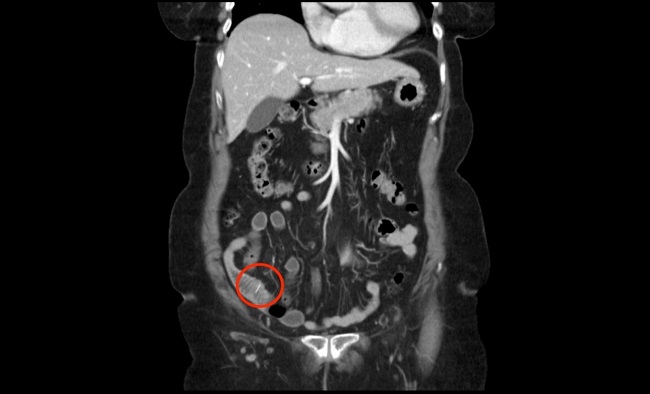

Ante la firme sospecha de abdomen agudo quirúrgico, previa valoración del equipo quirúrgico de guardia, se solicitó directamente una tomografía computarizada que mostró una perforación contenida de íleon distal secundaria a CE radio-opaco, como se aprecia en las imágenes 1 y 2.

Imagen 2. TC en proyección coronal. Imagen radioopaca a nivel de íleon terminal compatible con CE. Obsérvese como dato adicional, la impronta diafragmática por la cardiomegalia de la paciente, desplazando inferiormente el lóbulo hepático izquierdo.